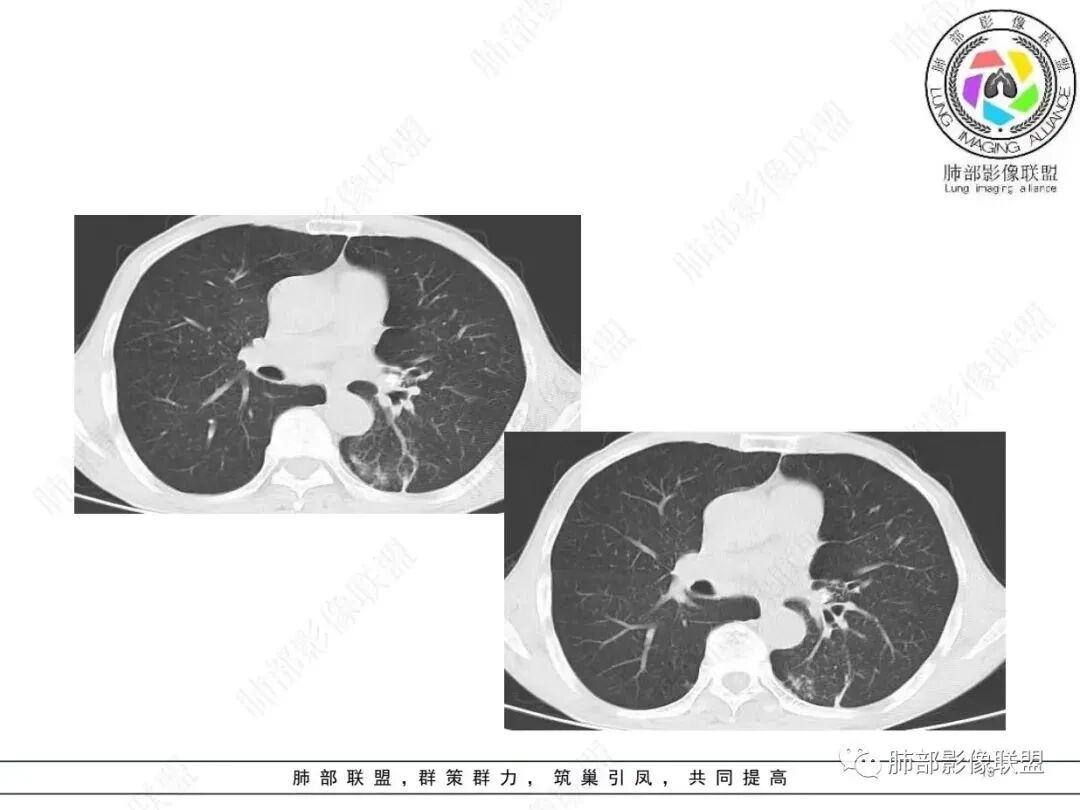

今天的病例从我的角度分析还是需要薄层

整体体积缩小,附近多发索条、斑点状高密度影,继发性结核肯定有,倾向于陈旧性,问题是:是否有继发的恶性肿瘤?薄层看看边缘是否毛刺?

南边:是否边界清楚GGO?

这是血管

3.影像表现双肺可见多发斑片状,条索及结节状高密度影,界不清,树芽征(+),考虑肺结核问题不大。左肺下叶背段结节病灶相对另类,应当警惕结核伴肿瘤,如腺癌。该病灶边缘有刀切征,未见典型分叶毛刺,结合周围有卫星灶,胸膜增厚粘连,可疑反晕,边缘有少许的磨玻璃样改变、较模糊,病灶周围有条索、树芽,相对强化较轻微,一元论考虑肺结核可能性大。腺癌如伴有磨玻璃多为中心实性成分周围为磨玻璃成分,且病灶膨隆为主、可见分叶、毛刺、胸膜凹陷、血管集束,脐凹征等征象,本例有轻微胸膜长线牵拉凹陷但其余肺癌常见恶性征象均不明显,且出现边缘平直等明显指向良性病变的征象。

左肺下叶片状影,边界不清,强化明显,更符合感染性炎性病变。